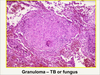

Histoplasmosis granuloma